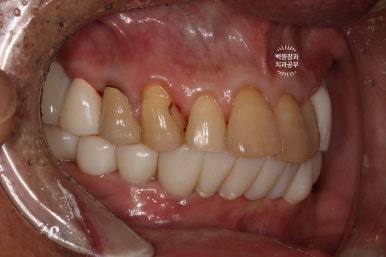

측면 사진에서도 상당히 깔끔하게 제작된 임플란트를 보실 수 있습니다!!!

최소한의 비용을 위하여 충치가 있었던 치아들은 간단히 레진으로 떼워 마무리해드렸습니다.

이렇게까지 제작해드리는데, 위턱에는 4개의 임플란트 아래턱에는 6개의 임플란트만 사용하였을 뿐입니다.

다행이라면 60대 남성분임에도 불구하고, 악궁이 작으신 편이라 12개의 치아만으로도 충분히 불편하지 않게 식사가 가능하셨습니다.